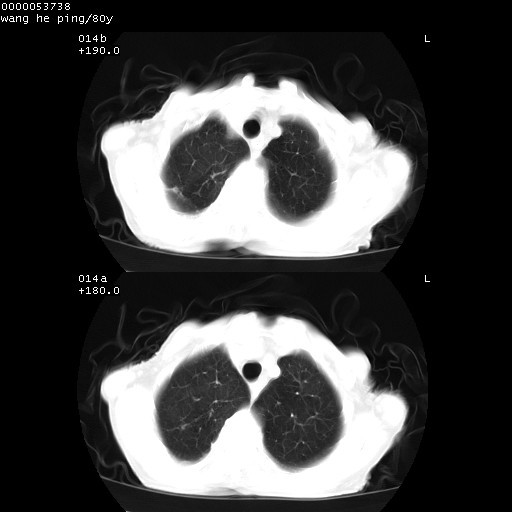

以下是引用黑白光影在2008-8-28 22:33:00的发言:[br]右肺中央型肺癌伴阻塞性肺炎,肺癌肺转移。

以下是引用lshx在2008-8-28 22:06:00的发言:[br]1.右肺中心型肺癌伴阻塞性肺炎,不除外双 肺早期转移。[br]2.心包积液。

以下是引用随光逐影在2008-8-29 7:40:00的发言:[br]1)右肺中心型肺癌伴阻塞性肺炎,肺内转移。2)心包积液(少量)。

以下是引用wqs571018在2008-8-28 21:56:00的发言:[br]右肺中心型肺癌伴阻塞性肺炎可能。

以下是引用liuyue在2008-8-28 22:46:00的发言:[br]1.右肺中心型肺癌伴阻塞性肺炎。[br]2.心包积液(少量)。